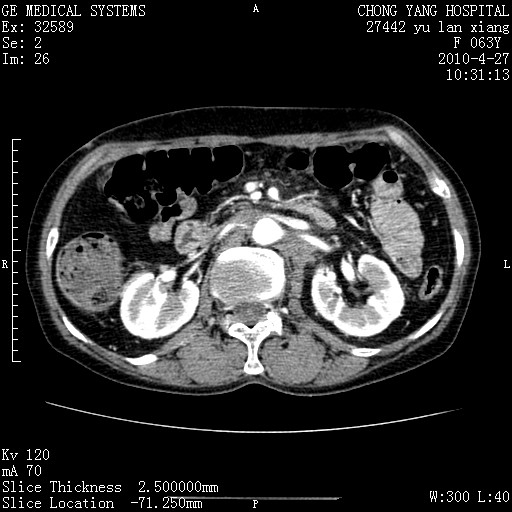

标题: CT26066:F63Y 上腹正中压痛半月,CA199:7400u/ml,MR示胰腺炎伴 [打印本页]

胰腺癌侵犯腹腔动脉干-分支、胃壁、左侧膈肌伴胰周及腹膜后淋巴结转移、胆囊切除术后。

胰腺癌侵犯腹腔动脉干-分支、胃壁、左侧膈肌伴胰周及腹膜后淋巴结转移、胆囊未显影。